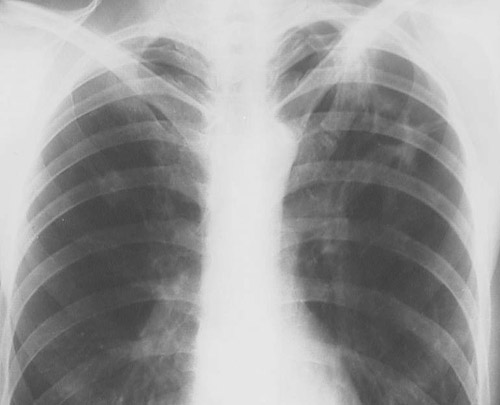

This chest radiograph reveals upper lobe granulomatous disease marked by irregular reticular and nodular densities and upper lobe cavitation due to the central caseous necrosis typical for tuberculosis.